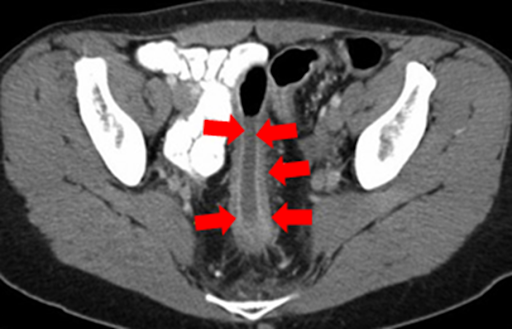

A patient presented with non-specific lower abdominal discomfort, urgency, and rectal pain. A contrast-enhanced CT abdomen and pelvis revealed circumferential mural thickening of the rectal wall with perirectal fat stranding and mucosal hyperenhancement, consistent with acute proctitis. No abscess formation or perforation was noted.

CT findings of proctitis typically include:

• Diffuse or segmental rectal wall thickening

• Hyperenhancement of the mucosa

• Perirectal fat stranding

• Preserved or obliterated rectal lumen

• Absence or presence of complications such as perforation, abscess, or fistula